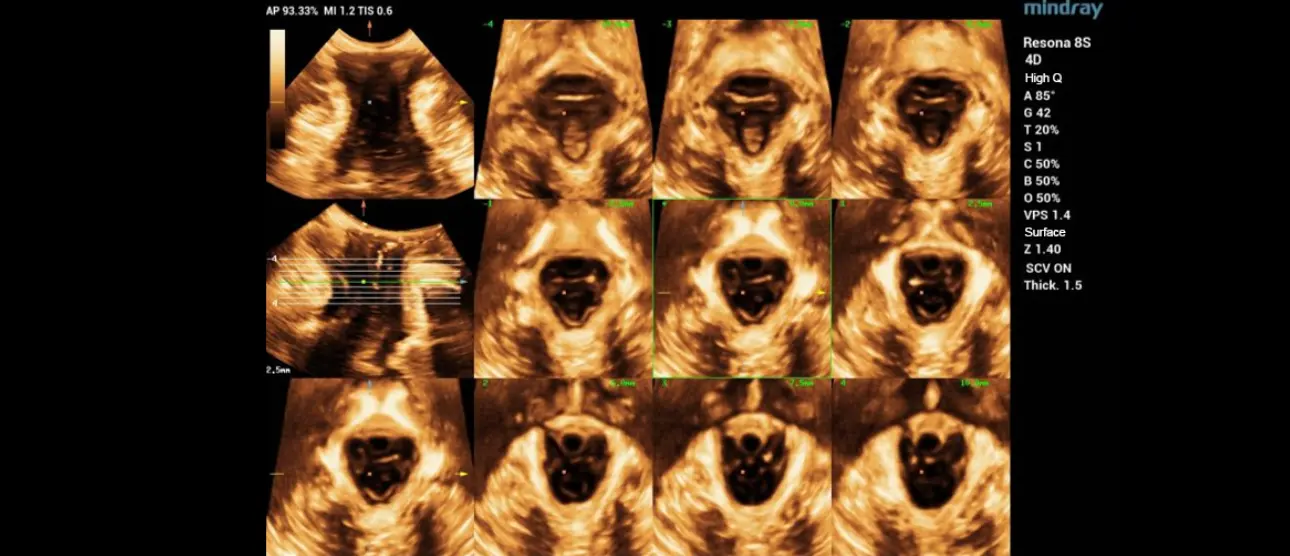

A significant development is Mindray's automated tomographic assessment of the anal sphincter, a first-of-its-kind innovation. In approximately 5% of women experiencing their first childbirth, the anal sphincter can sustain severe damage. Traditionally, obstetricians are familiar with suturing such tears. Now, the integrated software in these systems produces a standardized set of tomographic images with a simple push of a button, taking mere seconds. While some improvements are still needed, this progress marks just the beginning of exciting advancements in this field.